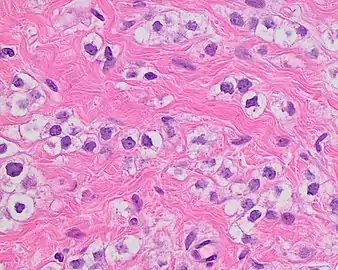

Invasive ductal carcinoma with moderate nuclear pleomorphism.

Invasive ductal carcinoma with marked nuclear pleomorphism.